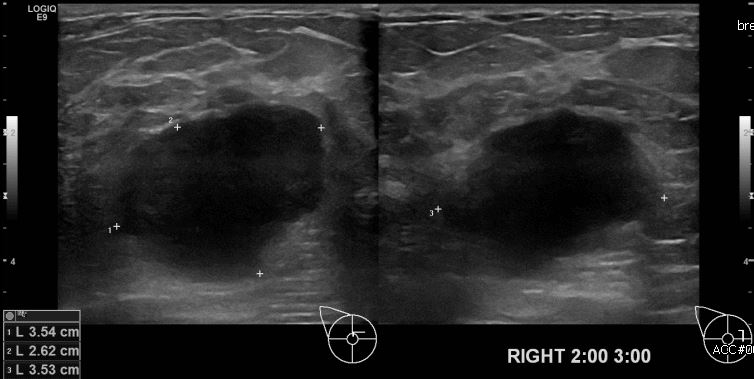

상기환자 유측 유방에 만져지는 멍울로 내원하신 50대 여성분으로 우측 2시에서

3시 방향에 만져지는 멍울 조직검사 시행하여 우측 침윤성 유관암 진단 되었습니다.